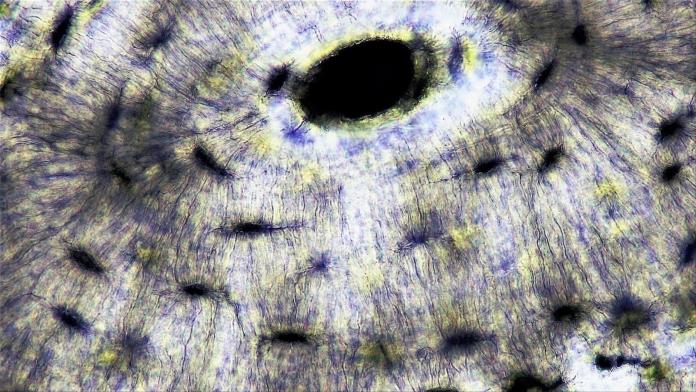

واستوحى الباحثون فكرة العمل الأساسية التي تقوم عليها مادتهم الجديدة من الآلية التي تقوم بها كل من العظام البشرية والشعاب المرجانية الملونة بتعديل رواسبها المعدنية استجابة للبيئات المحيطة بها.

يمكن للمواد الطبيعية تنظيم نفسها ذاتيا بالاعتماد على الموارد المحيطة بها، فمثلا تستخدم العظام إشارات قادمة من الخلايا للتحكم في إضافة أو إزالة المعادن المأخوذة من الدم حولها.

ولمحاكاة أدق لمنظومة عمل الجسم البشري ومكوناته، غمر الفريق شرائح بوليمرية من هذه المواد في سائل اصطناعي يحاكي التركيزات الأيونية لبلازما الدم البشري.

وبالفعل بعد غمر المواد في ذلك السائل، بدأت المعادن تتشكل على الأسطح. كما اكتشف الباحثون أنه يمكنهم التحكم في أنواع المعادن التي تشكلت عبر التحكم في التكوين الأيوني للسائل.

ثم أعد الباحثون دعامة مثبتة في أحد طرفيها فقط، وذلك لزيادة الضغط تدريجيا من أحد طرفي المادة إلى الطرف الآخر، ووجدوا أن المعادن تراكمت في المناطق ذات الضغط الأكبر. وكانت زيادة نسبة المعادن متناسبة طرديا مع الجذر التربيعي للإجهاد المطبق.